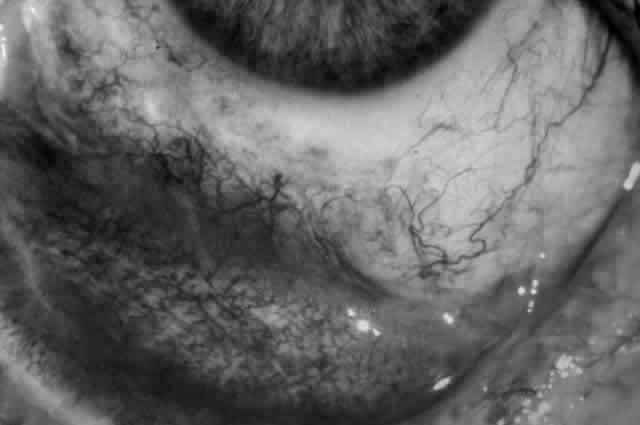

Clinically, the ocular disease in cicatricial pemphigoid (OCP) may present unilaterally in the form of a chronic, recurrent catarrhal conjunctivitis, but it eventually becomes bilateral. Subepithelial fibrosis is characteristic of stage 1 of OCP (Fig. 7). Stage 2 shows fornix foreshortening (Fig. 8), and symblepharon formation is the hallmark of stage 3 (Fig. 9). Stage 4, end-stage disease, is characterized by ankyloblepharon and surface keratinization (Fig. 10). Obstruction of the lacrimal ductules and meibomian gland ducts eventually produces an unstable tear film and progressive sicca syndrome, but it is to be emphasized that OCP is not a dry-eye syndrome until late in the disease course.20 Trichiasis and entropion occur because of the subepithelial fibrosis, with eventual keratopathy, corneal neovascularization, and corneal ulceration and scarring.20

Fig. 8. Stage 2 cicatricial pemphigoid, with fornix foreshortening and subepithelial fibrosis without frank symblepharon formation.